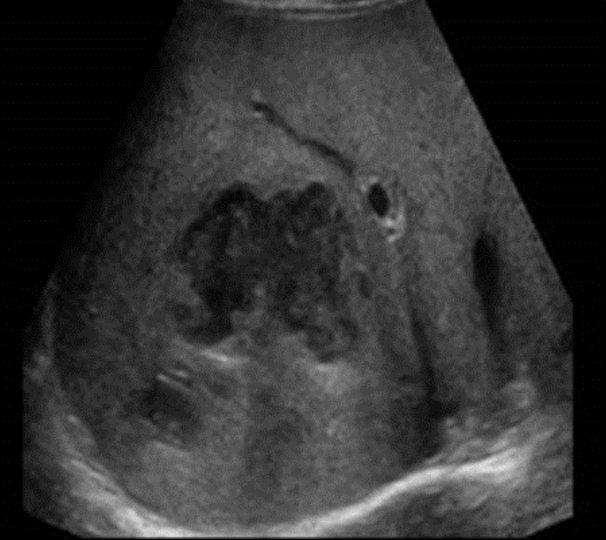

Pyogenic Abscess → pus-filled cyst formed d/t infection

clinical hx: infection (cholangitis, cholecystitis, serious GI infection), iatrogenic

s/sx: fever, increased WBC, anorexia, N&V, RUQ pain

2D US: round, indistinct border, acoustic enhancement, debris filled/can appear solid (echogenic, homogenous, isoechoic heterogenous, septations, altered internal echogenicity), thick echogenic wall

color doppler: no internal vascularity, peripheral vascularity

DDX: amebic abscess, hydatid cyst